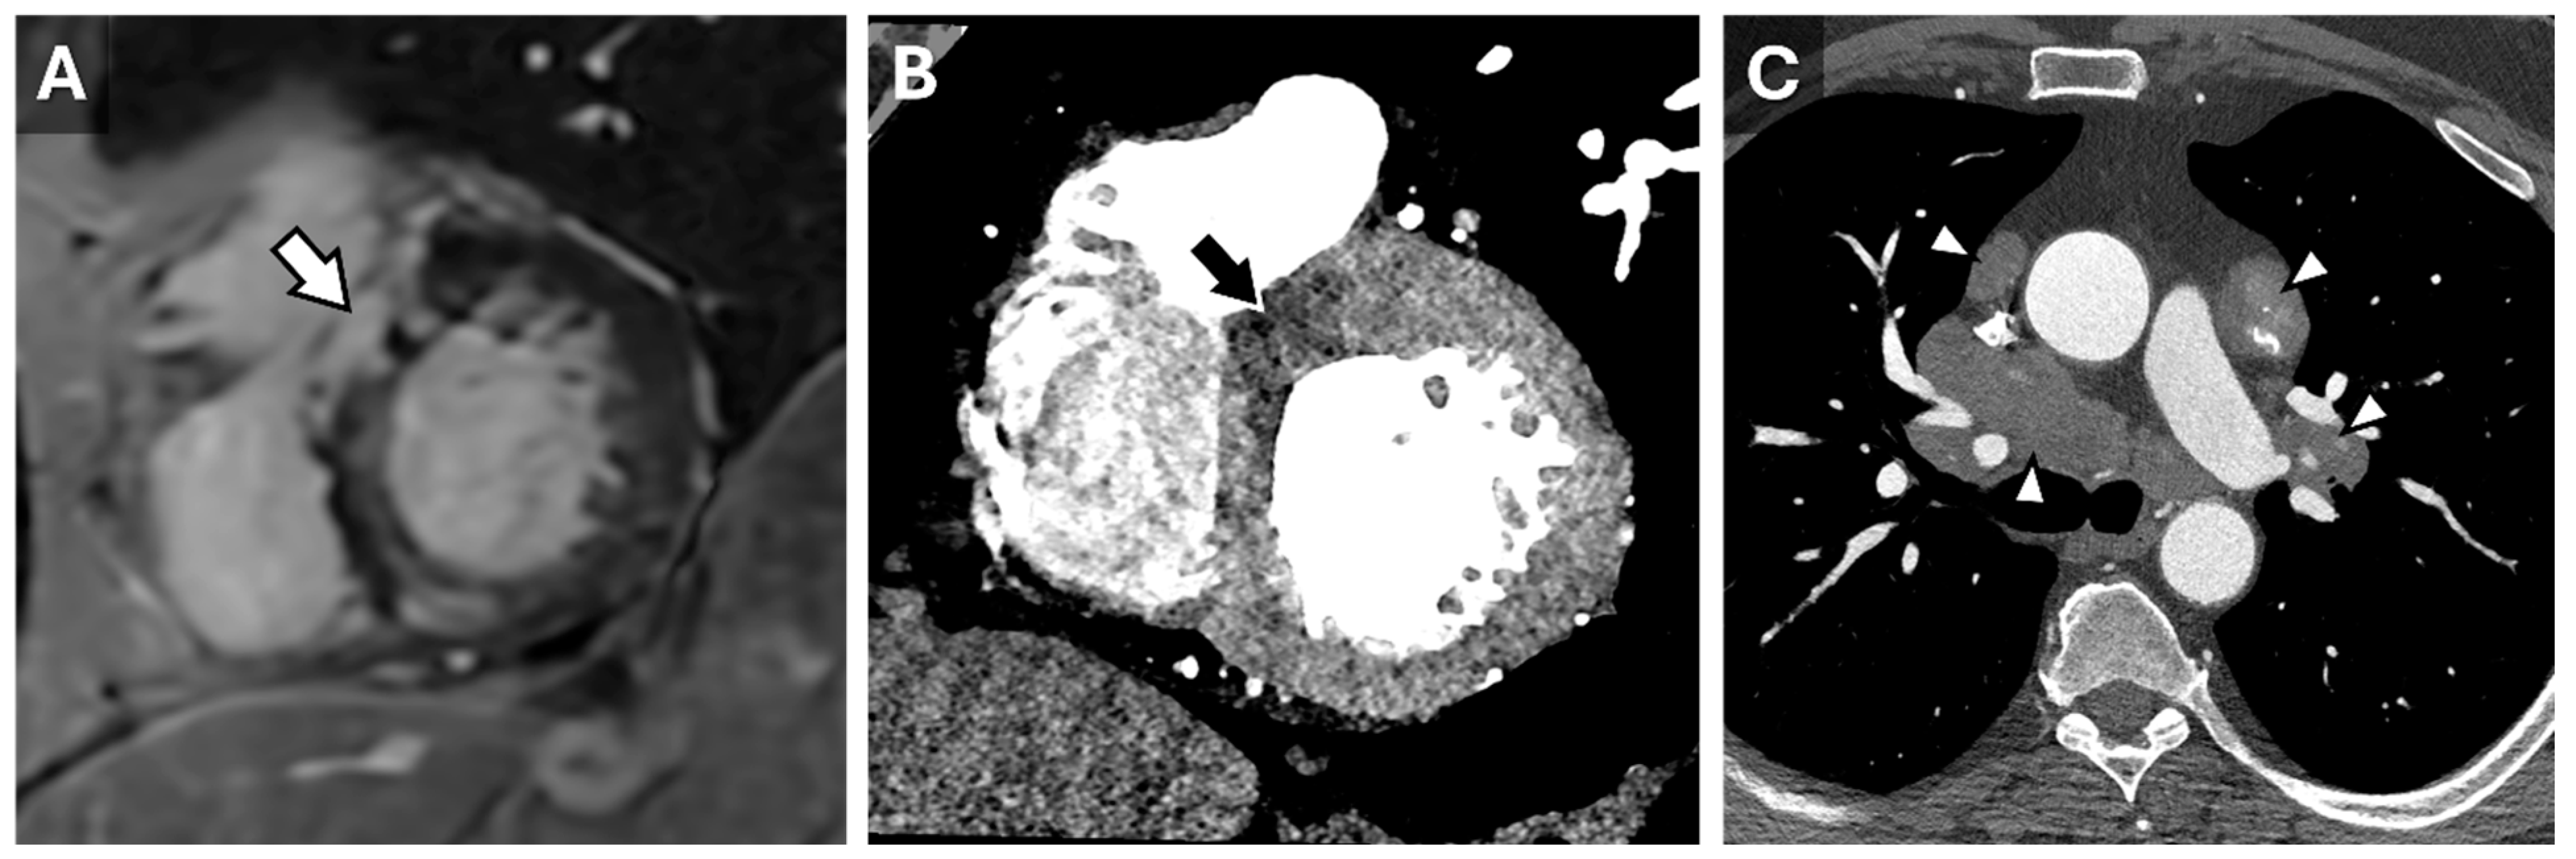

6. Hypertrophic Cardiomyopathy

- Bhasin, D.; Sharma, A.; Sharma, Y.P.; Singhal, M. Utility of Cardiac Computed Tomography in the Diagnosis of Apical Hypertrophic Cardiomyopathy: A Case Series. Heart Views 2024, 25, 86–91. [Google Scholar] [CrossRef]

- Jan, M.F.; Tajik, A.J. Modern Imaging Techniques in Cardiomyopathies. Circ. Res. 2017, 121, 874–891. [Google Scholar] [CrossRef] [PubMed]

- Dell’Aversana, S.; Ascione, R.; De Giorgi, M.; De Lucia, D.R.; Cuocolo, R.; Boccalatte, M.; Sibilio, G.; Napolitano, G.; Muscogiuri, G.; Sironi, S.; et al. Dual-Energy CT of the Heart: A Review. J. Imaging 2022, 8, 236. [Google Scholar] [CrossRef]